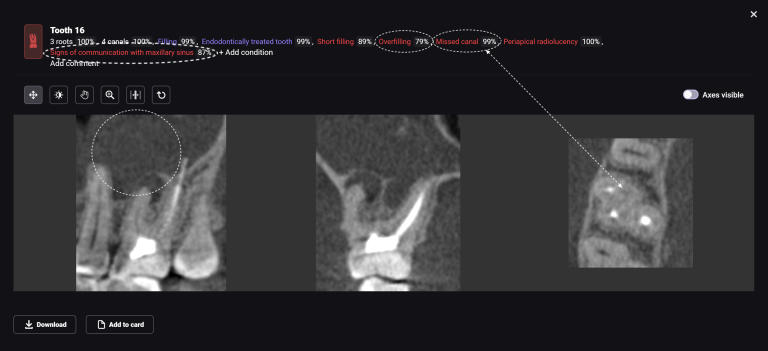

Planning implant placement using Diagnocat modules can help save the clinitian’s time and enhance the quality of implantological treatment

The result of collaboration with Diagnocat AI is a favorable outcome of the orthodontic and surgical stages of treatment